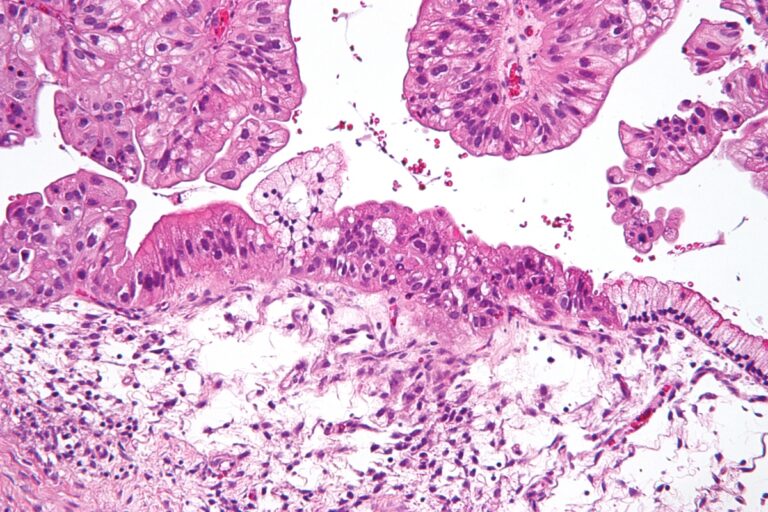

Όλες οι ασθενείς που συμμετείχαν στη δοκιμή είχαν χαμηλού βαθμού ορώδη καρκίνο των ωοθηκών, ο οποίος τείνει να προσβάλλει νεότερες γυναίκες.